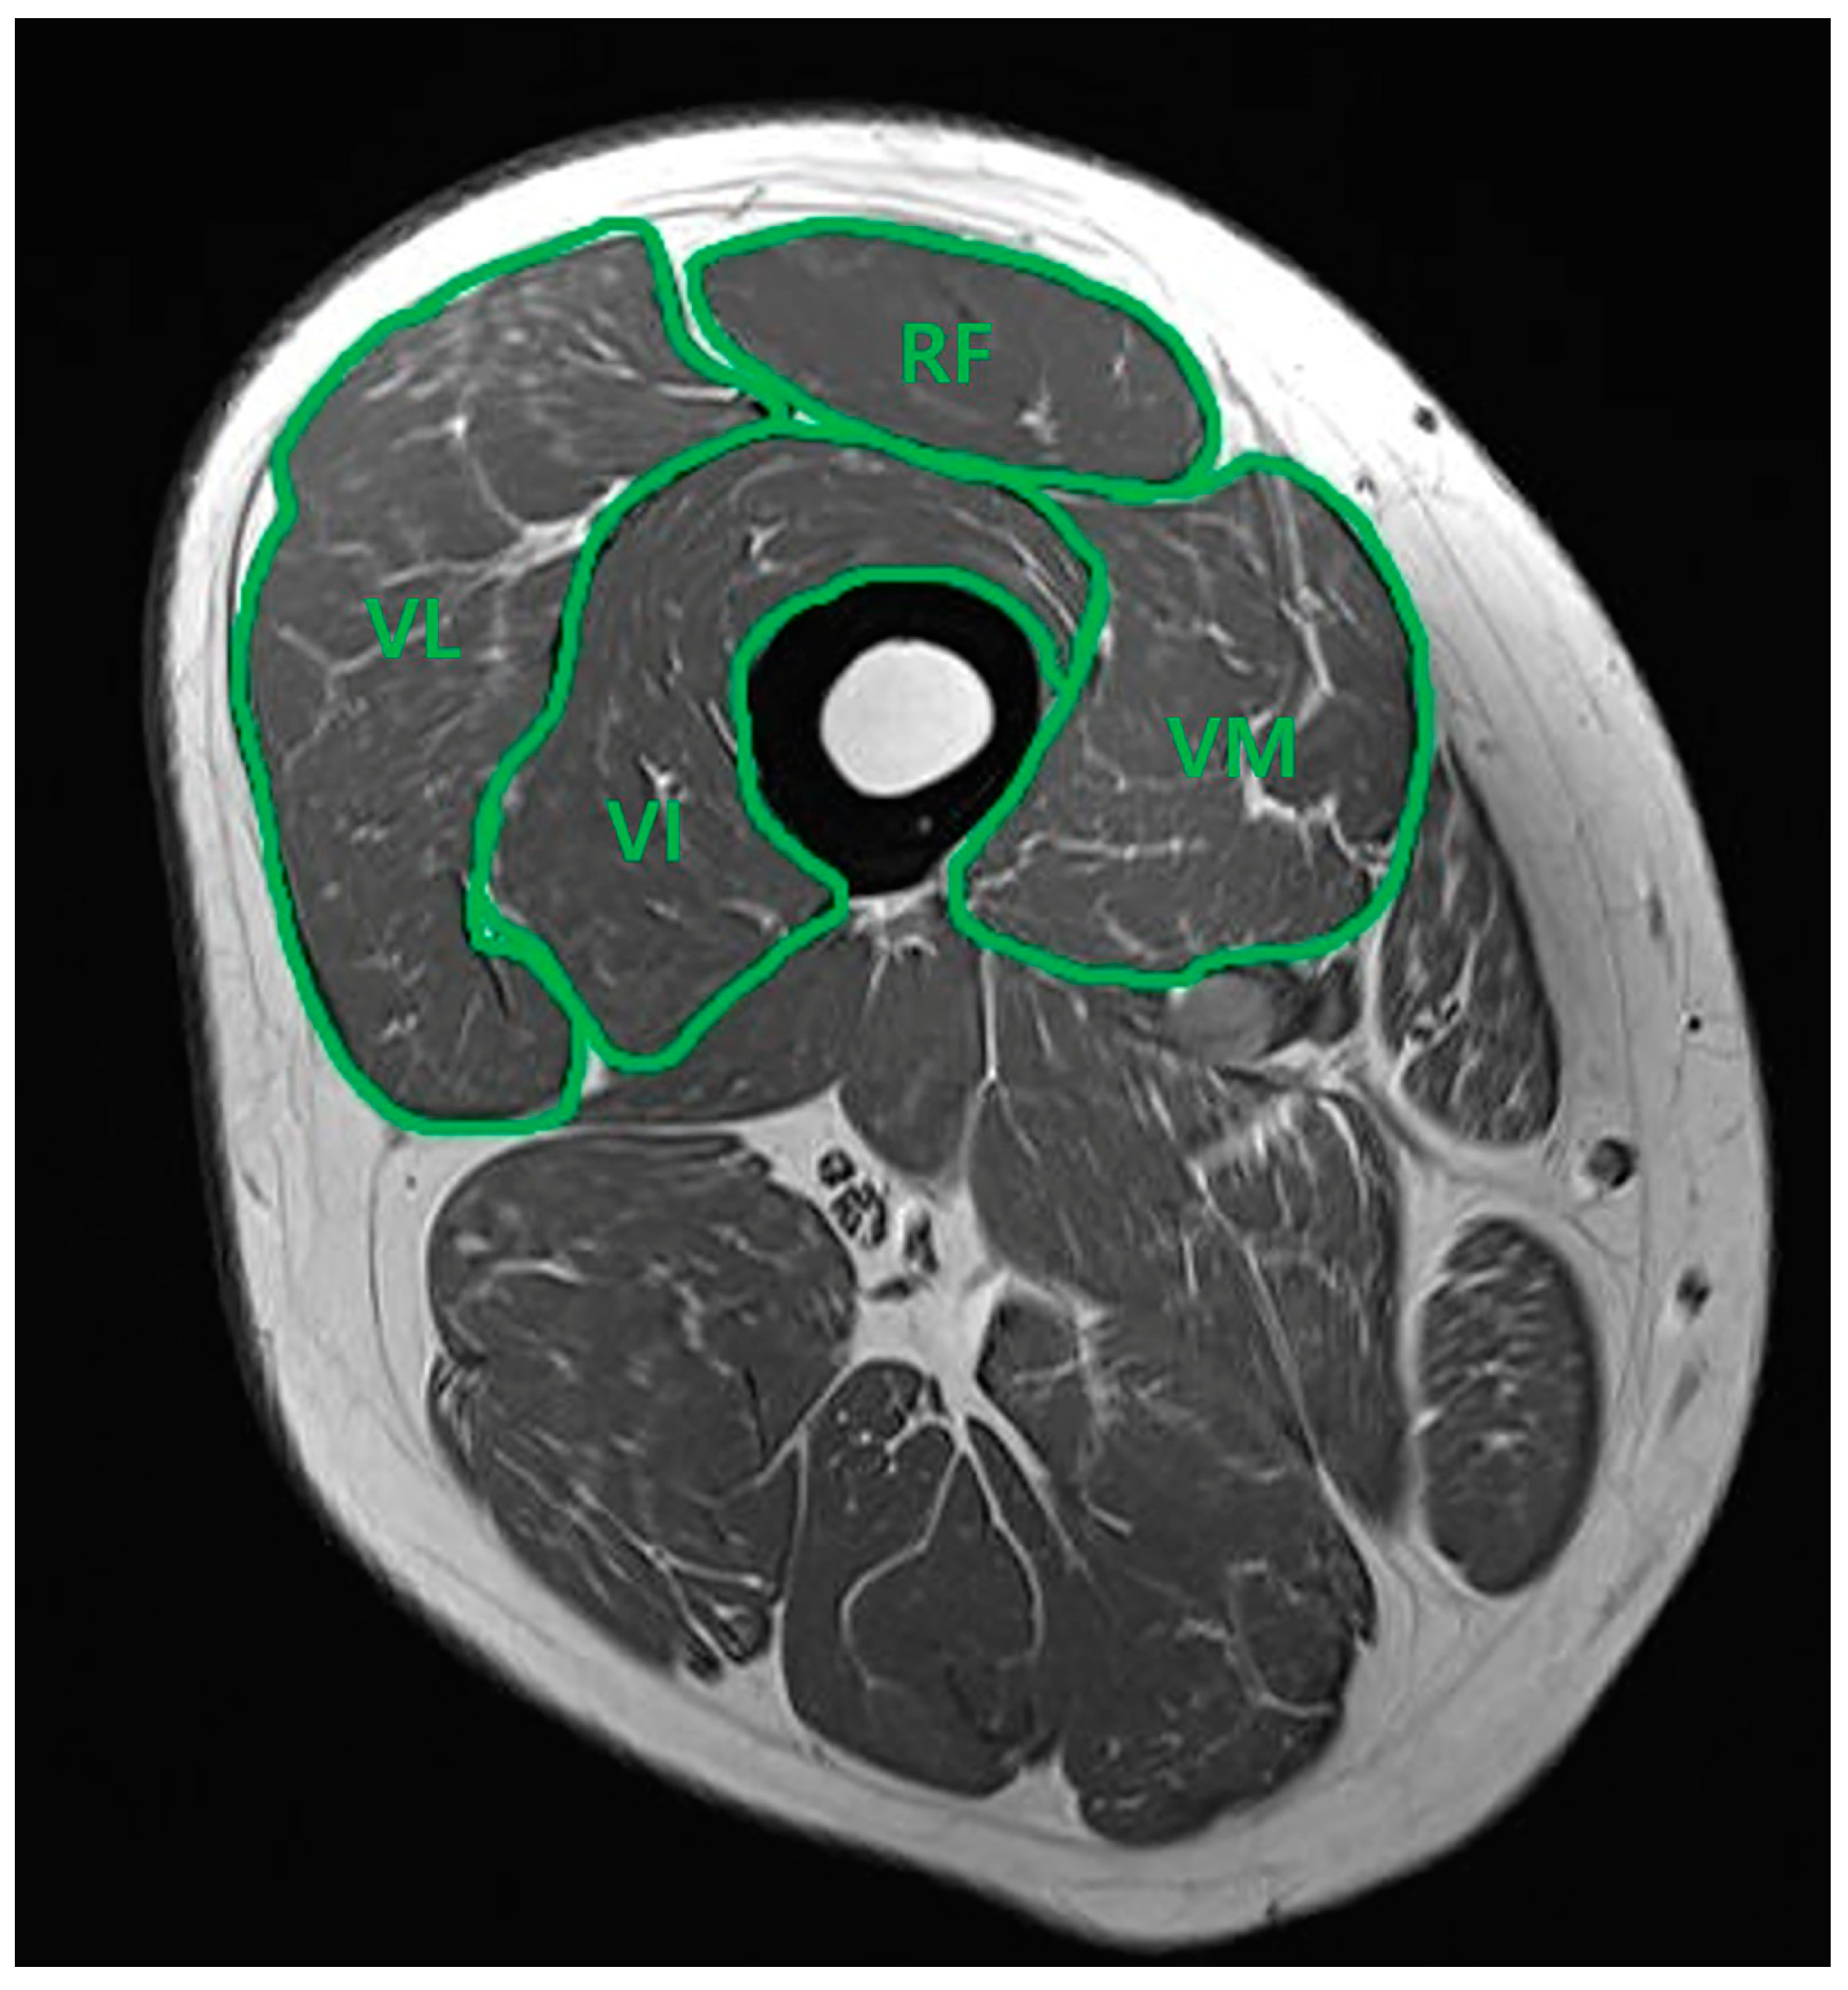

2.3. Thigh Muscle Cross-Sectional Area Measurement